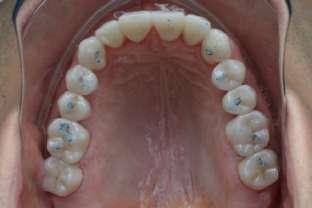

Si presenta alla nostra attenzione un paziente maschio, 35 anni, in apparente salute sistemica, fumatore, con la richiesta di controllare delle white spots, una leggera sensibilità e la richiesta di migliorare la luminosità del suo sorriso. Viene compilato e firmato il consenso informato. Il paziente viene motivato ad più efficace controllo del biofilm batterico e attraverso la condivisione dell’immagine clinica della topografia del biofilm batterico, (T.B.M.) scegliamo lo scovolino in gomma GUM Soft-picks (Sunstar) e lo sollecitiamo all’uso efficace degli spazi sovracrestali e allo spazzolamento in maniera delicata ma efficace della lingua. Sottoponiamo il paziente alla terapia parodontale non chirurgica con ablatore Comby touch (MECTRON) in modalità soft-mode per contenere la sua sensibilità. Valutiamo la sensibilità e modifichiamo i suoi stili di vita di igiene orale, di igiene alimentare e chiediamo di smettere di fumare. Il paziente riferisce di non essere disposto a rinunciare al fumo e chiediamo di ridurre il rischio di patologie e di discromie

da tabagismo passando all’uso dei dispositivi a tabacco riscaldato. Successivamente rileviamo il colore, con spettrofotometro, e con scala-colori Vita e documentiamo fotograficamente la condizione clinica presente.

Il colore rilevato è A2. Sottoponiamo il paziente ad uno sbiancamento pro-

fessionale con un principio attivo PAP (acido ftalimidoperossicaproico) che presenta il vantaggio di non sollecitare la sensibilità, pur mantenendo l’aspettativa di un risultato efficace nell’ottenere la luminosità del sorriso. Lo sbiancante ad uso professionale BRILLIANT LUMINA (Coltene), risulta essere per l’operatore di facile applicazione: ven-

gono protette le gengive con la diga liquida fotopolimerizzata, e si mescola il gel sbiancante lasciando cadere nel vasetto contenente 2 ml di gel, 3 gocce di liquido attivatore. Si ottiene il gel sbiancante di una consistenza ideale per una applicazione sulle superfici dentali sicura e pratica durante l’apposizione. Vengono eseguiti 4 step da 15 minuti.

Dopo ogni step viene aspirato il gel, pulite le superfici dentali con del cotone idrofilo e si riappone nuovamente il gel. Al termine dei 4 step, si aspira, si asciuga e viene tolta la diga. Si rileva e si condivide con il paziente il risultato ottenuto, A1, e viene documentato fotograficamente. Il paziente appare gioioso del risultato è favorevolmente colpito di non aver sofferto durante il trattamento di sensibilità. Alla persona assistita sono stati programmati dei follow-up per il trattamento successivo delle white spots con applicazioni di resine infiltranti e rigenerazione guidata dello smalto.